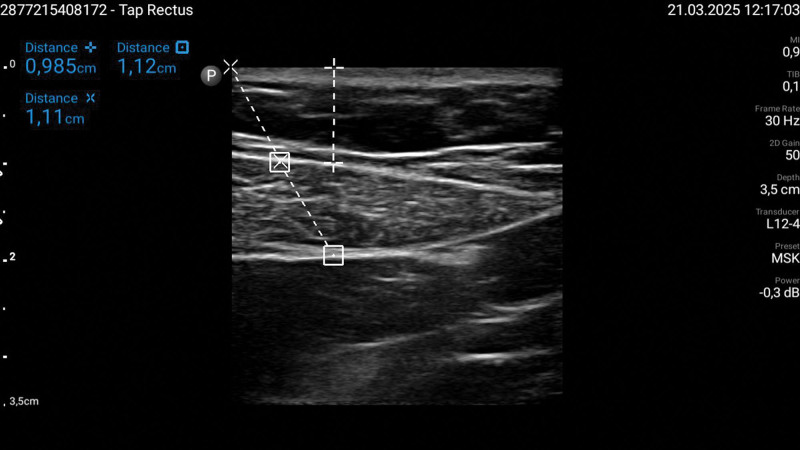

Recent findings: Current evidence supports the use of RA techniques such as transversus abdominis plane (TAP) block, quadratus lumborum (QL) block, erector spinae plane (ESP) block, and intraperitoneal instillation of local anesthetics in reducing postoperative pain and opioid consumption. While TAP and ESP blocks improve postoperative analgesia, the QL block offers longer-lasting pain relief. Intraperitoneal local anesthetic administration has shown potential in decreasing opioid use and improving respiratory recovery. Additionally, port-site infiltration remains a simple yet effective alternative. However, anatomical challenges in obese patients necessitate optimized ultrasound guidance for successful block placement.